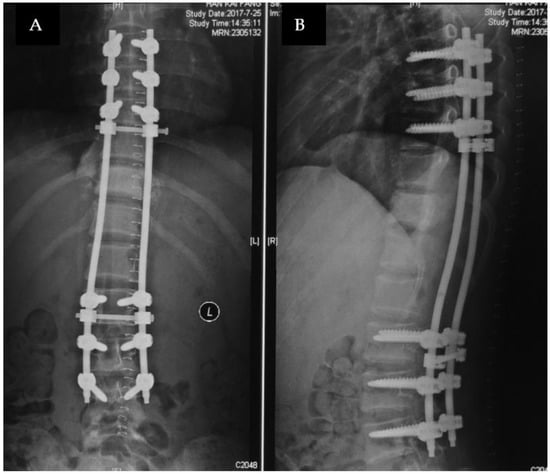

2.2. Treatment